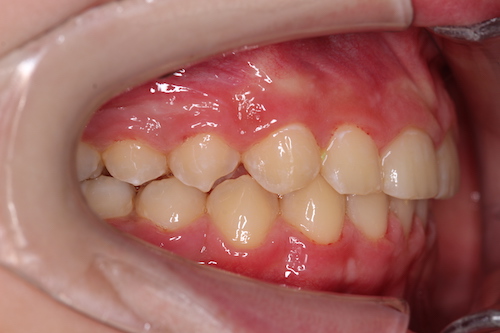

После